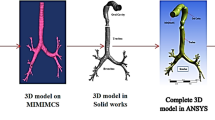

Geometry processing sequences are established to allow the simulation of the effects of obstructions in the 3D lung topology. This approach enables the investigation of the impact of any narrowings on the airflow into the lung, by employing a CFD simulation. The proposed sequences are implemented directly on an already available 3D model of the lung [29], obtained from CT scans, by utilising state-of-the-art techniques. A Laplacian mesh contraction procedure in the direction of the inward normal is executed to iteratively apply contractions to the surface of a certain segment of the mesh. Several correction procedures are applied to mitigate degradation effects and abnormalities. Furthermore, the lung geometry is splitted into various parts, such as the generations and the outlets, as depicted in Fig. 1, to facilitate the analysis.

Structural modeling

Structural modelling of the lung must include all the features that describe the geometry of the lung either in detailed (e.g., 3D mesh) or in consice manner (e.g., 1D representation). Specifically, the 3D model is obtained from CT scans by employing state-of-the-art techniques and it consists of the set of vertices V, the set of edges E and the faces F. The 1D representation of the lung is extracted by applying skeletonization [31] approaches directly to the 3D model. In particular, the 3D mesh is iteratively contracted (simplified) to a zero-volume mesh until each node to be connected to three or only one nodes. The subsequent 1D representation consists also of a set of vertices V and edges E.

Physical modeling of the lung

Various methods, such as surface reconstruction, surface remeshing, triangulation, and decimation are employed for cleaning-up the lung geometry, in order to enable smoothness and accelerate the upcoming techniques of volume meshing and solving. A smoothing process is considered compulsory to minimize any adverse effects on the study results, since the CFD analysis could be affected by additional edge effects created by the deformation of the airway geometry. Furthermore, our analysis will not be disturbed much by the structural modeling procedures, since the airflow into the lungs is essentially resolved by the topology of the generations’ geometry rather than the surface arrangement of the airways.

An open source platform associated to CFD and FPT analyses, called OpenFoam [38], is efficiently employed, in order to implement the volume meshing of the lung by utilizing the snappyHexMesh algorithm. A very fine discretization near the walls of the pulmonary system is adopted by our analysis that involves hex-dominant cells. In this manner, the stimulating properties of turbulence can be discerned, while the positions of particles can be precisely determined. Specifically, the domain is discretized into 5,569,106 cells, which denote a huge computational burden. In order to effectively tackle this issue, ARIS, a high performance computer (HPC), was utilized to conduct the involved simulations.